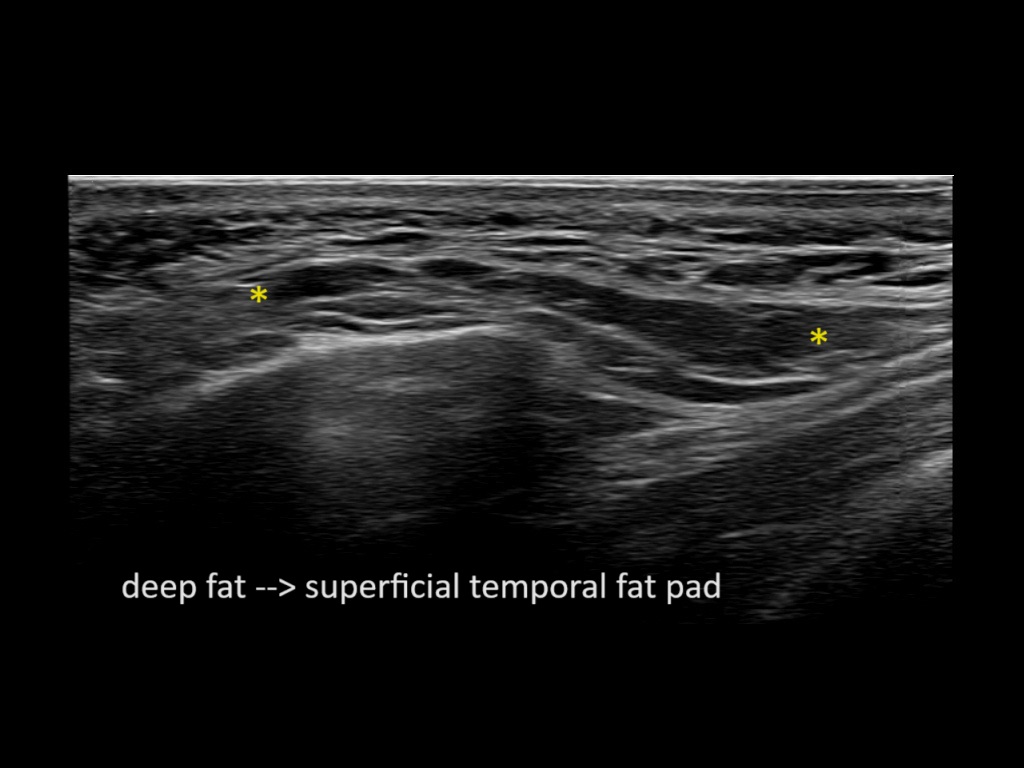

Filler behavior - Temple zygoma US

Study the first image to recognize the different layers. If you are sure about the layers, swipe to the second image to view the answer (if applicable).

Hover over an image to view the secondary image or click on the image title for more information.